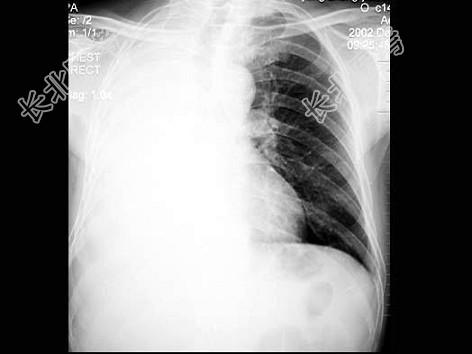

- 单项选择题男,65岁, 胸痛,胸片检查如图, 下列诊断中最可能的是 ( )

A、右肺胸膜肥厚

B、右肺不张

C、右侧胸腔积液

D、右肺炎症

E、以上都不对